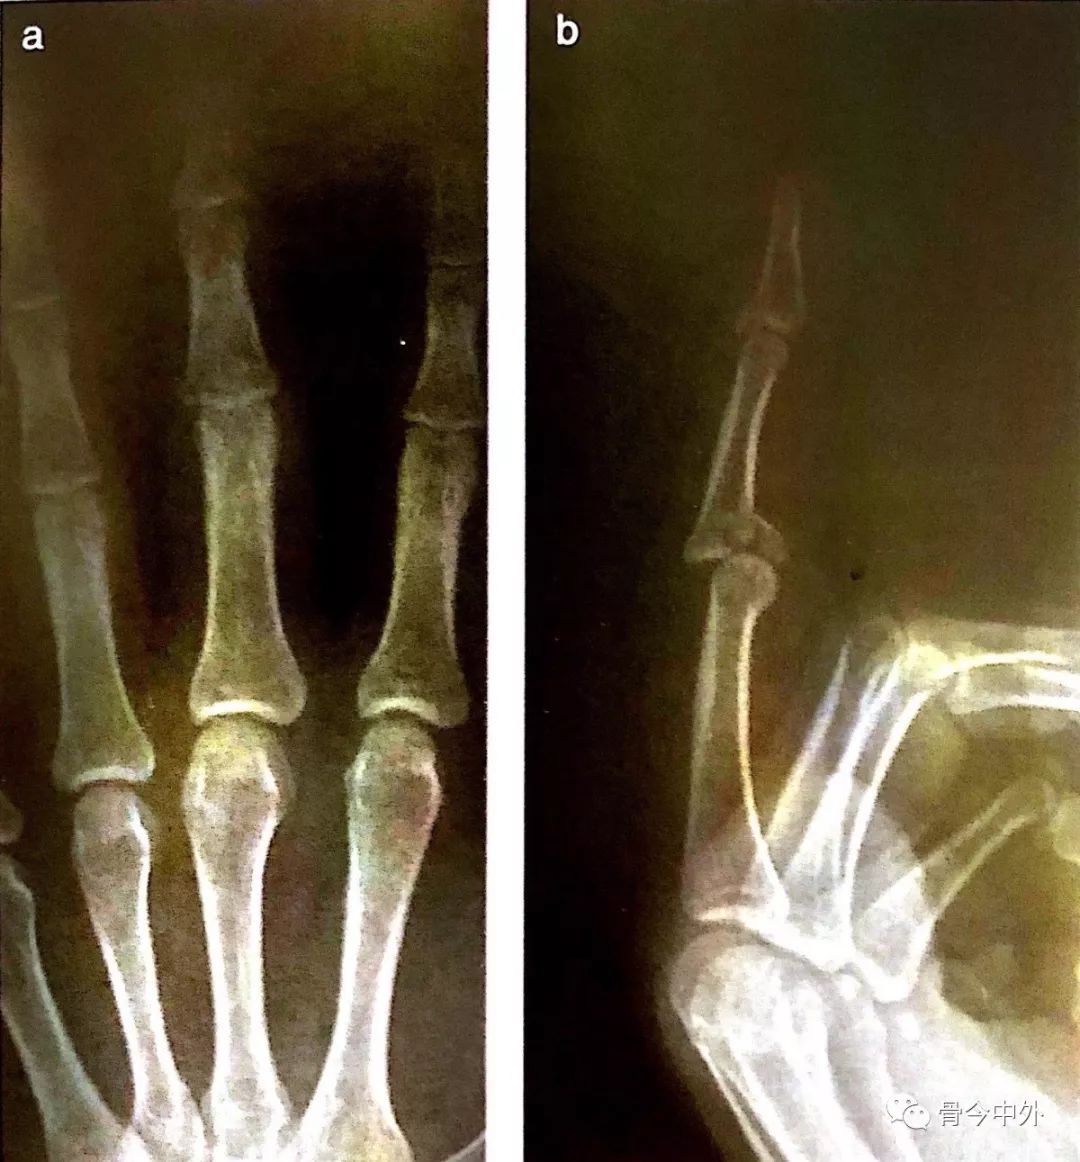

诊断: 右手小指末节指骨撕脱骨折;右手小指锤状指畸形 治疗:取右手小指远节手指背侧S型切口,暴露末节指骨基底部,见伸肌腱止点处撕脱骨折,骨折块为末节指骨背侧骨块,骨块含少许关节面软骨,该骨块向背侧近端移位,断端间瘢痕组织填充,指间关节半脱位。 予以清除断端间软组织,先复位远指间关节,由指端向近端一枚克氏针贯穿固定于背伸位,检查指间关节固定好。 再于中节指骨背侧中远1/3 カラバオ杯トッテナム戦で先制ゴール後、右手小指を負傷 チェルシーは現地時間1月5日、カラバオカップ準決勝第1戦でトッテナムをで下したなか、先制ゴールの際、ドイツ代表MFカイ・ハフェルツが右手を負傷。 相手GKと交錯した際に小指を骨折したようだと海外メディアが伝えている。 本拠地スタンフォード・ブリッジにトッテナムを迎えたチェルシーは前半5分、ペ カラバオ杯トッテナム戦で先制ゴール後、右手小指を負傷 チェルシーは現地時間1月5日、カラバオカップ準決勝第1戦でトッテナムをで下したなか、先制ゴールの際、ドイツ代表MFカイ・ハフェルツが右手を負傷。 相手GKと交錯した際に小指を骨折したようだと海外メディアが伝えている。 本拠地スタンフォード・ブリッジにトッテナムを迎えたチェルシーは前半5分、ペ

近指间 Pip 关节背侧骨折与脱位 实例讲解5种手术方式 骨今中外 微信公众号文章阅读 Wemp